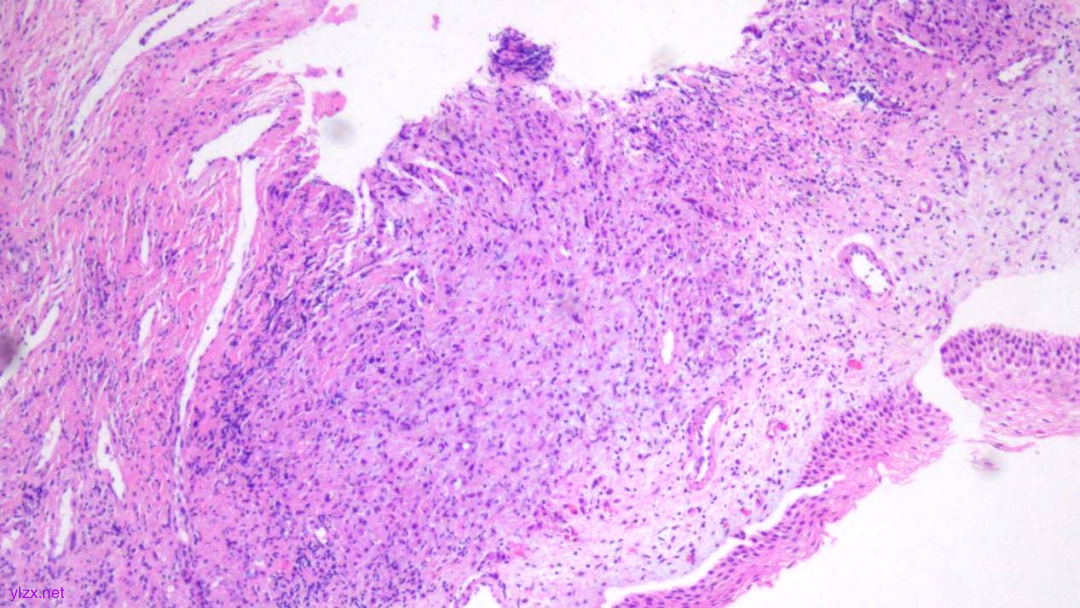

HE:

1.宫颈2点、10点:鳞状上皮下间质内见瘤组织弥漫增生,胞浆宽阔,红染,核小,较一致,部分细胞核偏位,部分细胞可见核仁;

2.宫颈5点:鳞状上皮下间质内见少量异型细胞巢,核增大,深染,浆红染,少量细胞浆内见黏液,印戒样;宫颈管搔刮组织:见血凝块、宫颈内膜组织,间质见异型细胞条索,形态同宫颈5点。

鳞状上皮下间质内见瘤组织弥漫增生,胞浆宽阔、红染,核小,较一致

瘤细胞排列偏稀疏,核小,深染,胞浆红

间质内见异型细胞巢,核增大,深染

间质内见异型细胞条索,核增大,深染,浆红